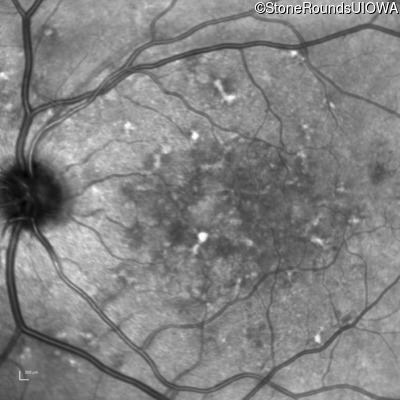

Infrared Fundus Photograph - Right - 20/250

Exemplar